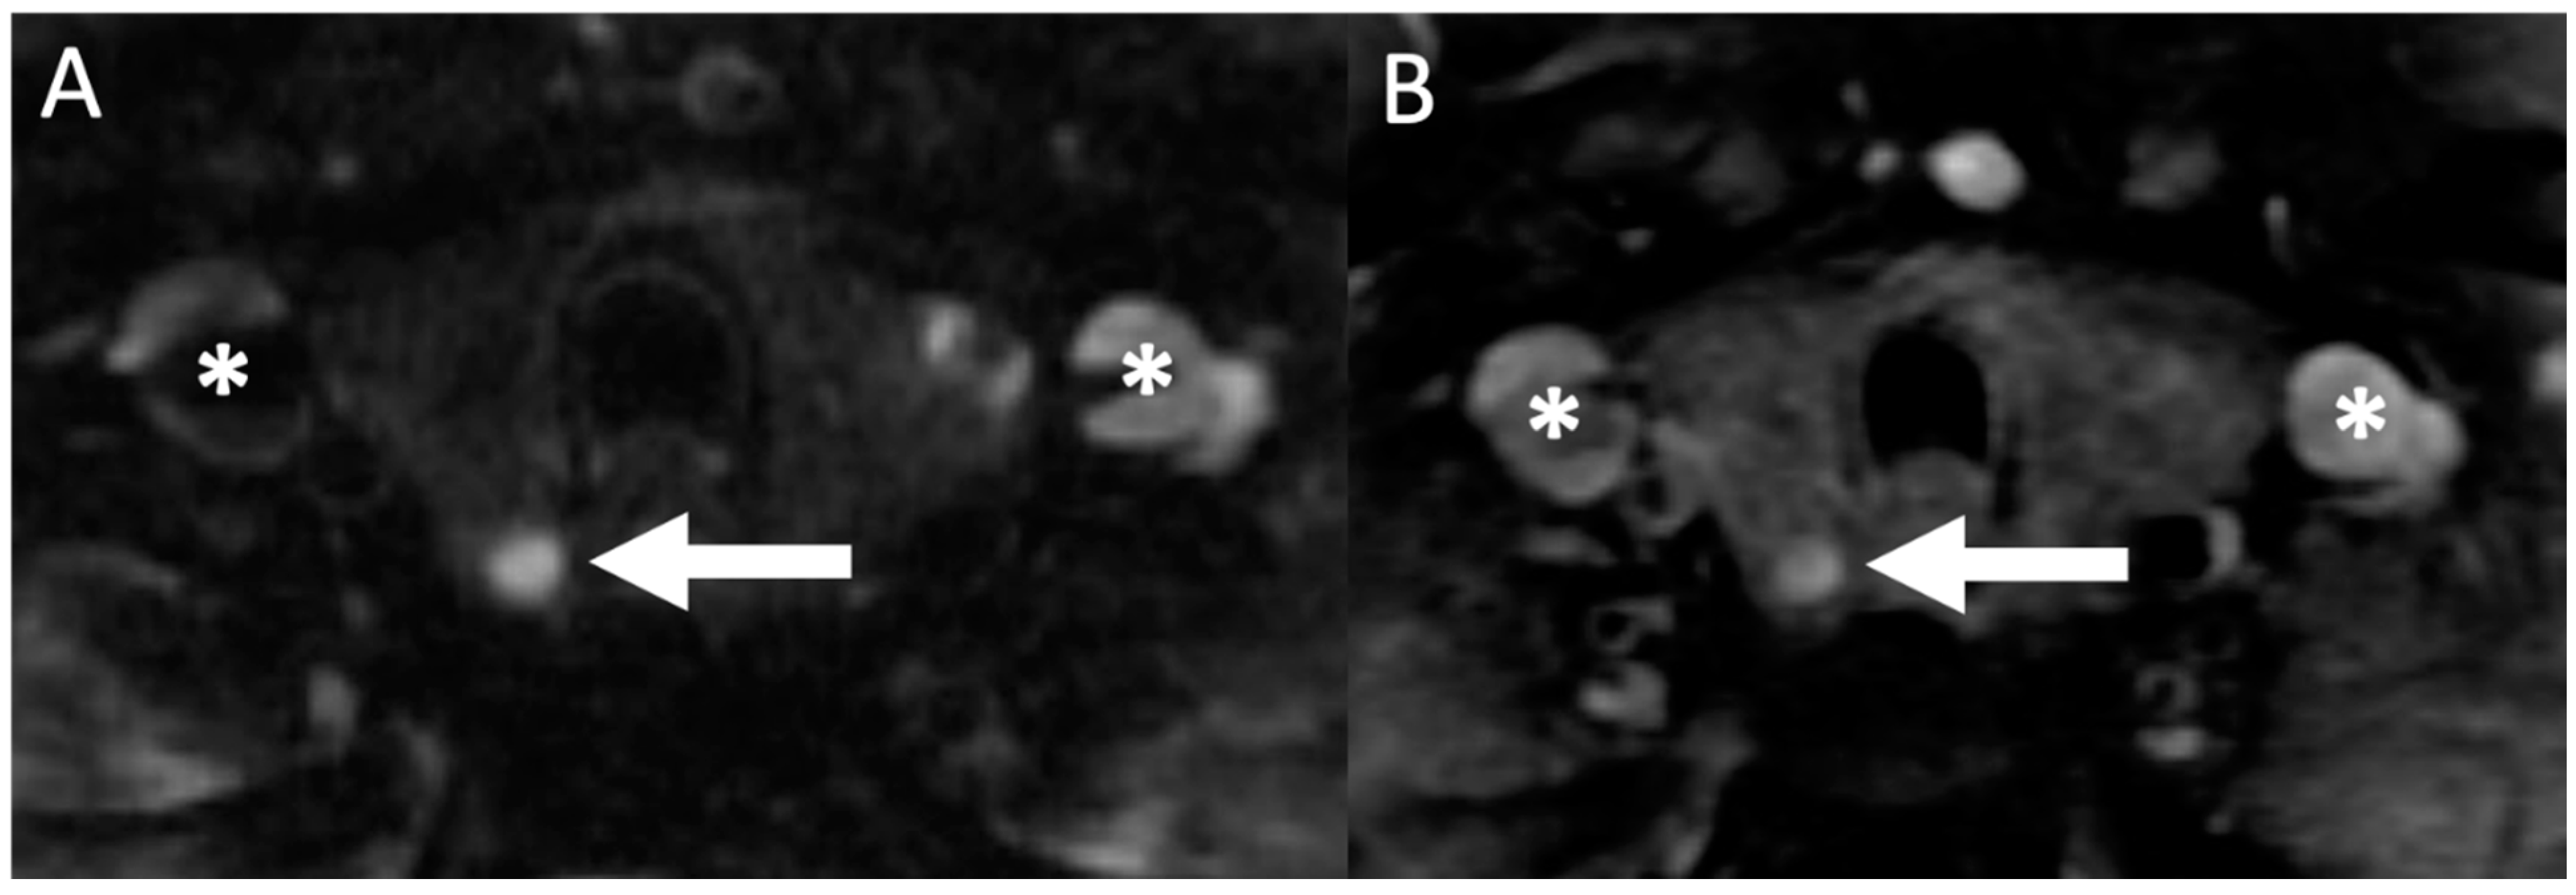

- Sacconi, B.; Argirò, R.; Diacinti, D.; Iannarelli, A.; Bezzi, M.; Cipriani, C.; Pisani, D.; Cipolla, V.; De Felice, C.; Minisola, S.; et al. MR appearance of parathyroid adenomas at 3 T in patients with primary hyperparathyroidism: What radiologists need to know for pre-operative localization. Eur. Radiol. 2015, 26, 664–673. [Google Scholar] [CrossRef]

- Argirò, R.; Diacinti, D.; Sacconi, B.; Iannarelli, A.; Diacinti, D.; Cipriani, C.; Pisani, D.; Romagnoli, E.; Biffoni, M.; Di Gioia, C.; et al. Diagnostic accuracy of 3T magnetic resonance imaging in the preoperative localisation of parathyroid adenomas: Comparison with ultrasound and 99mTc-sestamibi scans. Eur. Radiol. 2018, 28, 4900–4908. [Google Scholar] [CrossRef]

- Yildiz, S.; Aralasmak, A.; Yetis, H.; Kilicarslan, R.; Sharifov, R.; Alkan, A.; Toprak, H. MRI findings and utility of DWI in the evaluation of solid parathyroid lesions. La Radiol. Med. 2019, 124, 360–367. [Google Scholar] [CrossRef] [PubMed]